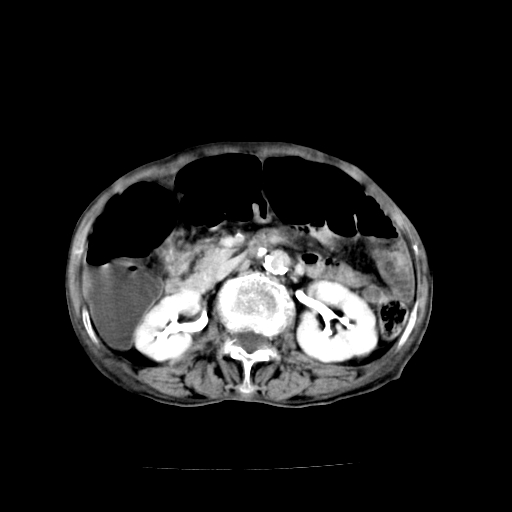

标题: CT19149:女,68岁,腹胀、恶心两周。 [打印本页]

标题: CT19149:女,68岁,腹胀、恶心两周。

女,68岁,腹胀、恶心两周,先做ct平扫,当时家属不同意强化,6天后家属要求增强扫描。

1、胃窦癌; 2、局灶性脂肪肝。

1、胃窦癌?建议行胃镜!; 2、局灶性脂肪肝。

1.局灶性脂肪肝;2.胃窦癌可能,建议行进一步检查。

1)不排除胃窦癌;建议行胃镜检查。 2)局灶性脂肪肝。

1)不排除胃窦癌;建议行胃镜检查。 2)局灶性脂肪肝。腹水。

考虑:胃窦ca,腹水,脂肪肝

1)胃窦壁厚,考虑胃窦癌?建议行胃镜检查。 2)局灶性脂肪肝。

支持考虑1、胃窦癌?建议行胃镜!; 2、局灶性脂肪肝。  3、双侧胸腔积液,胸膜增厚

不均匀脂肪肝,胃腔改变须结合钡餐或胃镜观察

1)局灶性脂肪肝。2)胃窦癌可能,建议行胃镜检查。